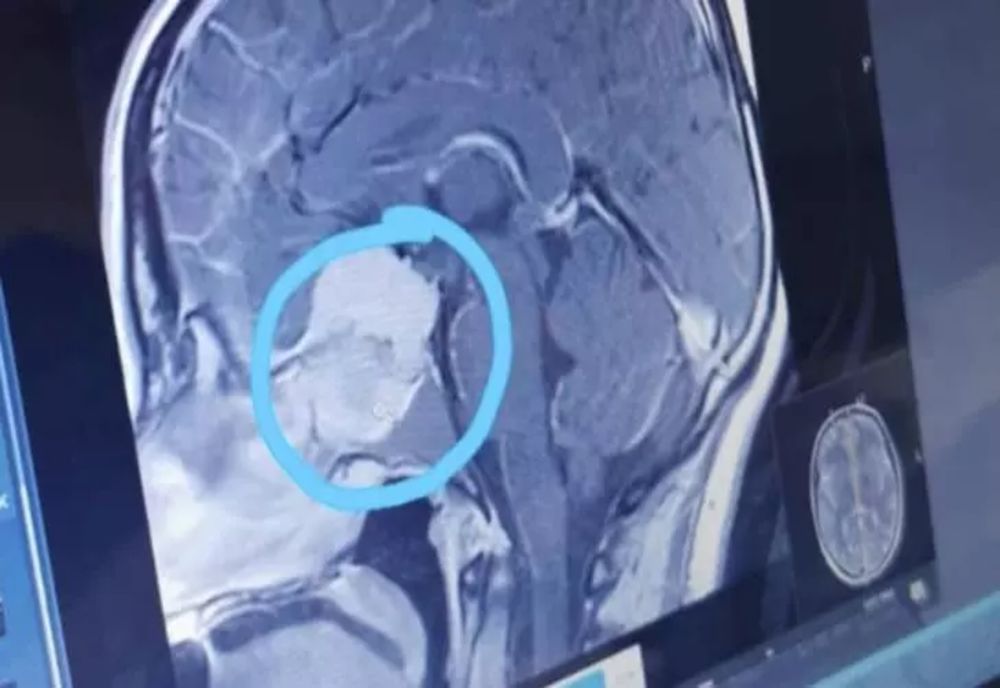

12 iun. 2022, 19:01ActualitateȘoc în lumea presei. Ovidiu Ioanițoaia a suferit un accident vascular cerebral